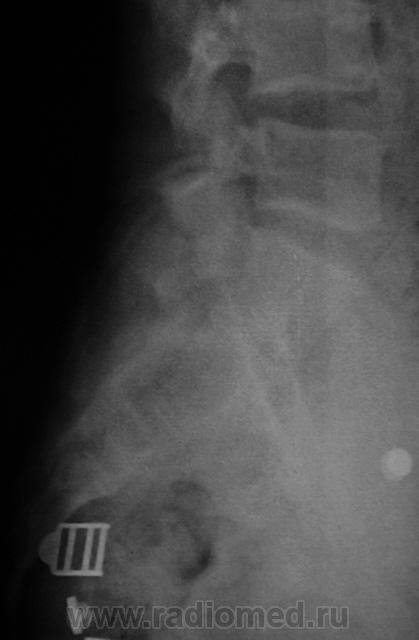

Мнение по снимкам: плохая подготовака - много газов и каловых масс в проекции L4-L5, крестца и копчика. Выпрямленность поясничного лордоза. Дугообразный сколиоз вправо.

Пациент пнул по мячу и упал. Боли при сгибании туловица. Этим также обусловлена "плохая подготовка" - не готовили.

Травматолог видит переломы.

ИМХО: вариант строения крестцово-подвздошных суставов( во-первых :тени "линий переломов" симметричные слева и справа, во-вторых: по механизму травмы, что бы возникли такие переломы после удара по мячу...- не может быть!).

Сия "бяка" носит название переходного двустороннего симметричного подвижного, с образованием неоартроза с двух сторон пояснично-крестцового позвонка. Так вот эта ситуация МОЖЕТ проявить себя болевым симптомом при физической нагрузке, в т.ч. и при "заштатных" движениях в поснице, мало как он этот удар производил и куда его в это время "повело" и как....

Виктор Григорьевич, не нужно так усложнять! Будем точнее и проще - двустороняя суставная сакрализация L5!

Люмбализация, сакрализация... Переходный позвонок!!! И все.

Рассматривая ещё раз снимки (тем паче отличного качества Т-граммы Валентина Львовича), ловлю себя на мысли, что у нас бы больной попал-таки на КТ (линейные Т-граммы не производим...) и что как бы не пропустить начальные стадии б-ни Бехтерева!..